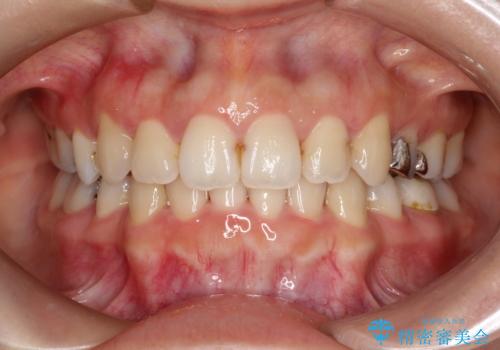

【インビザライン】前歯のガタガタを治したい

- 前歯のガタガタを主訴に来院されました。

上の歯の前突も気になってたため、奥歯の遠心移動も行いながらインビザラインにて治療を行いました。

今回は奥歯の遠心移動とIPRを行って配列しています。